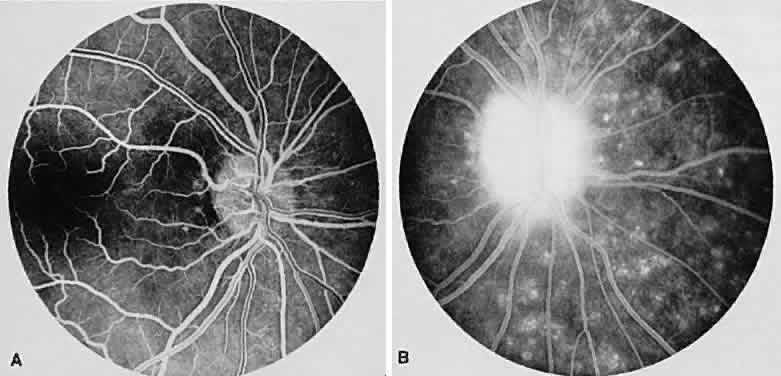

Birdshot retinochoroidopathy (also known as vitiliginous chorioretinitis) presents bilaterally, generally in middle-aged women, causing floaters and decreased vision, night blindness, and color blindness. Clinically, there are patches of postequatorial choroidal and retinal pigment epithelial depigmentation (Fig. 10A), vitreous cells, macular and disc edema, and venous sheathing. SRNV frequently is a late sequela. Often central vision may be preserved in at least one eye.

Fig. 10. Birdshot retinochoroidopathy. A. Multiple cream-color deep choroidal lesions. B. Fluorescein angiogram shows leakage of the optic disc and the retinal vasculature. C. Indocyanine green angiography showing areas of hypofluorescence that exceed those observed on fluorescein angiography.

On fluorescein angiography, retinal vessel staining, disc leakage, and cystoid macular edema are found (see Fig. 10B). There often is generalized hypofluorescence of the retinal vessels and increased circulation time.35,36 Surprisingly, the patches of depigmentation may appear normal on angiography, although there can be mild late hyperfluorescence.35,36 Posterior pole choroidal hyperfluorescent lesions that correspond to the areas of depigmentation and SRNV also can be seen.37

On ICG angiography (see Fig. 10C), early and late hypofluorescent patches, exceeding the clinically detectable lesions, with a choroidal vasotropic distribution and relative sparing of the peripapillary area and the central macula, are noted. These findings differentiate this condition from AMPPPE, multifocal choroiditis, and other granulomatous conditions such as sarcoidosis and sympathetic ophthalmia. Rarely, hyperfluorescent spots are noted in the late phases of the angiogram, which correspond ophthalmoscopically to retinal inflammation or obstructive changes.38